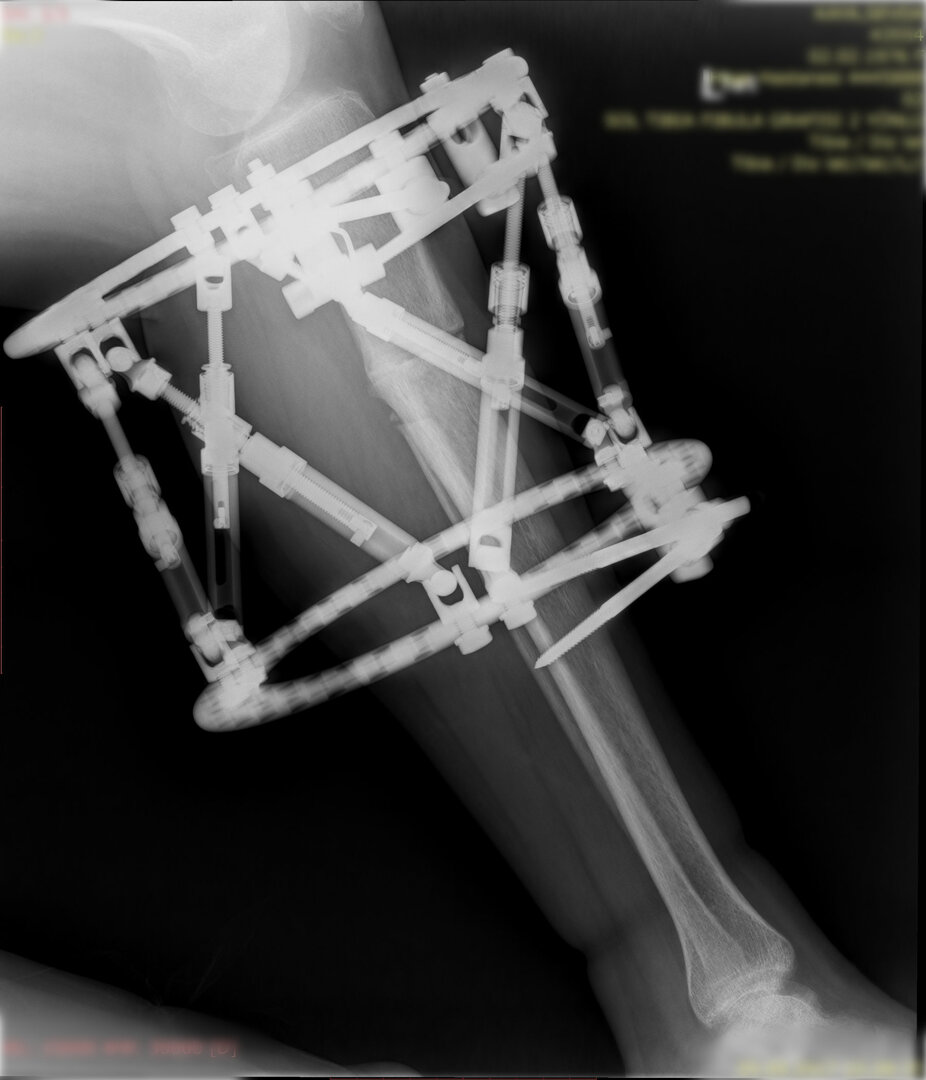

Deformitenin yeri ve miktarına bağlı olarak bilgisayar destekli sirküler eksternal fiksatör ile tedrici düzeltme yapılabilir. Bu sistemin avantajı düzeltme esnasında sistemle oynayarak yeni düzenlemeler yapmanıza izin vermesidir.

Bu ameliyat öncesi bir deformite analizi yapılıp hangi kemikte, normalden ne kadar sapma olduğu tespit edilir. Daha sonra bu kemiğe yine ostetomi yapılarak bu anormal sapma düzeltilir.  Bu düzeltme plak-vida veya intramedüller çivi ile akut olarak düzeltilebileceği gibi bilgisayar destekli sirküler eksternal fiksatör ile tedrici olarak ta yapılabilir. Hangi yöntemin hangi hasta için uygun olacağına hasta özelinde karar veriyoruz, ne tür cerrahi tedavi olması gerektiğini danışabilirsiniz.

Büyütmek için üzerine tıklayınız.